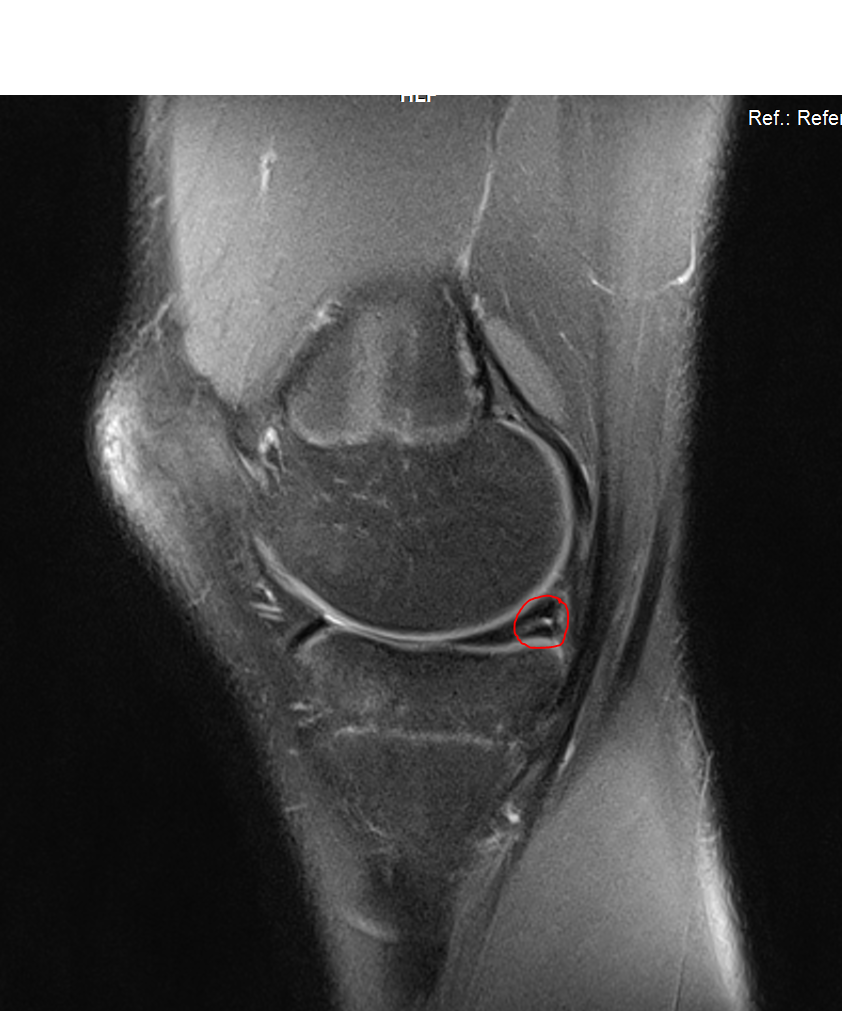

Wie stark also der gerissene Meniskus auf den benachbarten Knorpelflächen gerieben hat. Diverse Sportarten wie zum Beispiel Tennis Fußball oder Skifahren belasten ihn stark. Meniskusriss und -schaden.

Eine eindeutige und für alle Fälle geltende Antwort gibt es darauf nicht. Bei einer Meniskusverletzung der inneren Zone hat hingegen eine Heilung des Schadens keine gute Chance deswegen muss der verletzte Meniskusanteil operativ abgetragen werden. Sprungsportarten wie Volleyball oder Disziplinen mit abrupten Stopps und schnellen Drehungen wie Tennis oder Squash.